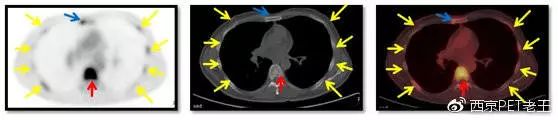

我们又把CT调整到骨窗,看骨骼病变的情况,可以看到全身绝大部分骨骼都有转移,但骨质结构破坏不明显(中列),说明这种是早期的骨转移,如下图:

红色箭头:胸椎转移;黄色:肋骨转移;蓝色:胸骨转移